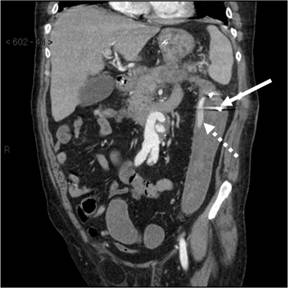

Shortly after the procedure, the patient developed three episodes of massive haematochezia overnight. An urgent CT scan demonstrated a splenic artery pseudoaneurysm and haemorrhage from the splenic artery into the splenic flexure of the colon and blood in the descending colon (Figures 1 and 2).

Figure 2. Coronal reformatted CT image demonstrates the position of the percutaneous drain in the colon lumen (arrow) and extravasated intravenous contrast mixed with unopacified blood in the descending colon (interrupted arrow). |